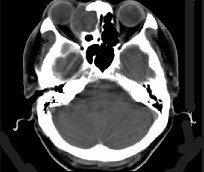

患者,女性70岁,因双眼视力骤降半天就诊。检查:右眼视力0.02,左眼0.03,结膜无充血,角膜透明,角膜后沉着物阴性,瞳孔对光反射对称、迟钝,晶状体轻度混浊,玻璃体无混浊;视乳头充血水肿。(如图)请问首选需行哪种检查()

-

患者,女性70岁,因双眼视力骤降半天就诊。检查:右眼视力0.02,左眼0.03,结膜无充血,角膜透明,角膜后沉着物阴性,瞳孔对光反射对称、迟钝,晶状体轻度混浊,玻璃体无混浊;视乳头充血水肿。

如VEP为各波潜伏期延长、波幅下降;眼底荧光造影为视盘高荧光;视野为巨大中心暗点;CT无异常;视力下降经验光试镜无法矫正。则诊断为()

- 患者,女性70岁,因双眼视力骤降半天就诊。检查:右眼视力0.02,左眼0.03,结膜无充血,角膜透明,角膜后沉着物阴性,瞳孔对光反射对称、迟钝,晶状体轻度混浊,玻璃体无混浊;视乳头充血水肿。下列有关本病的治疗原则中错误的为()